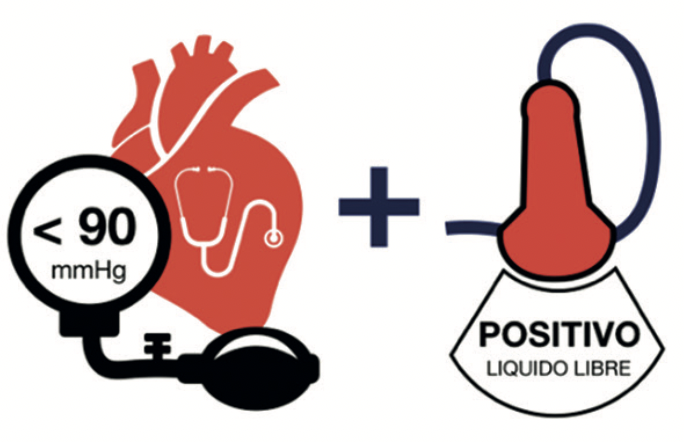

Daniel Roizblatt Krell, Juan Pablo Ramos Perkis, Pablo Arellano Graell, Patricio Araya Cortés

|

|